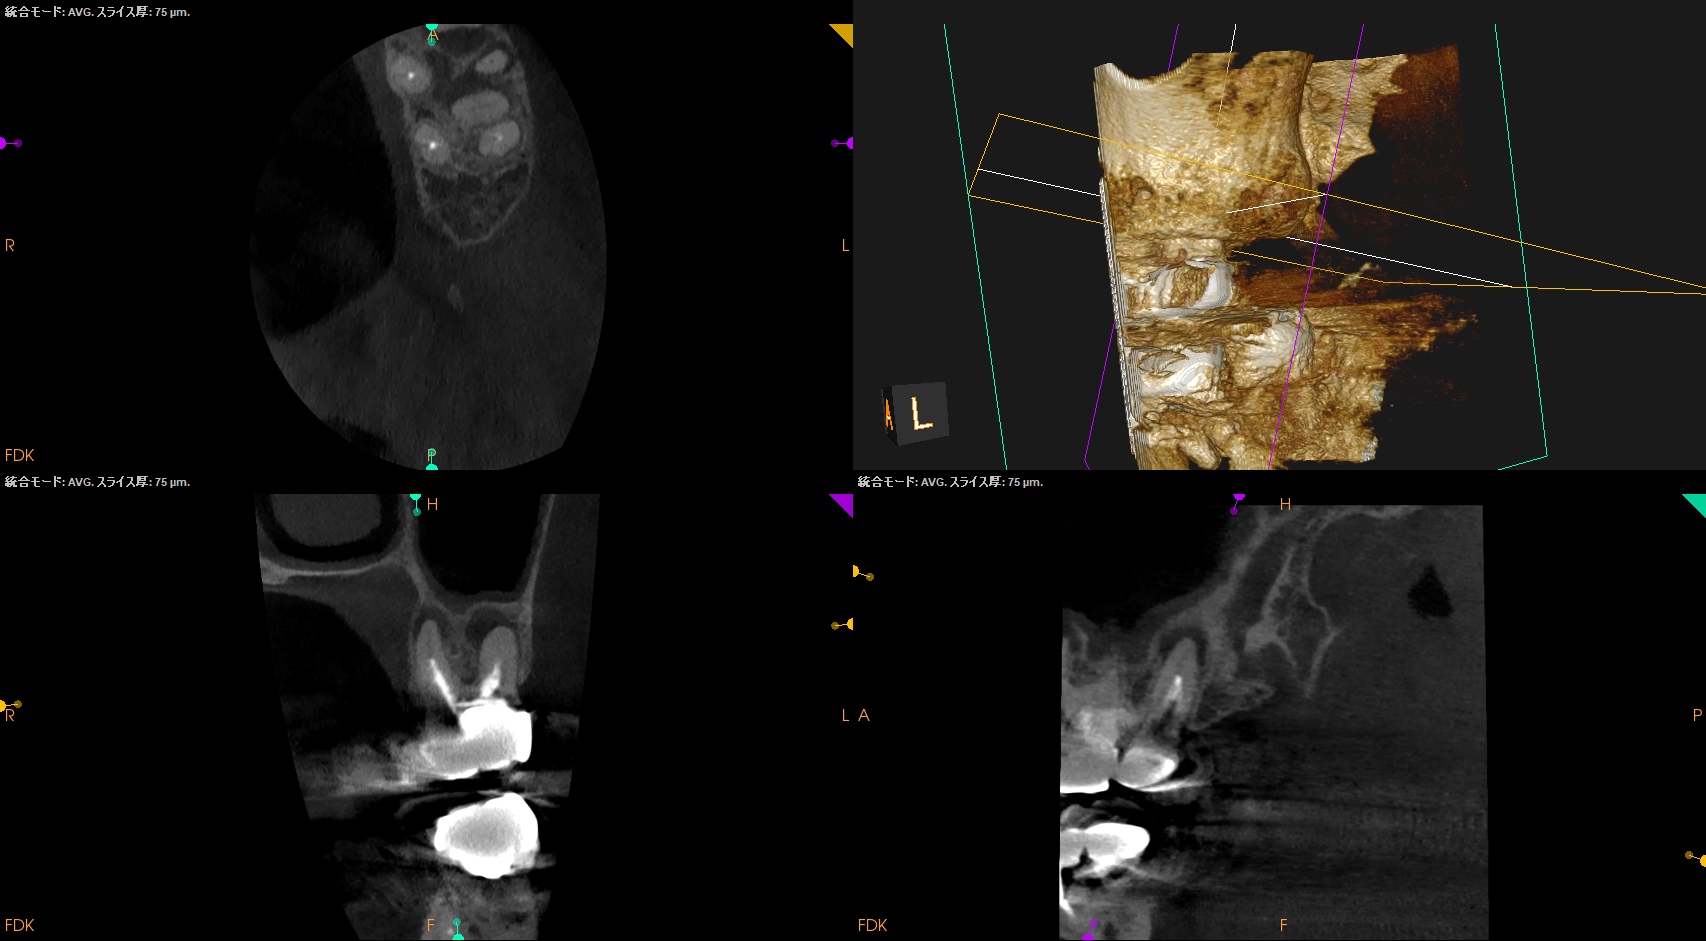

まず第2大臼歯から。

MB

MB2

DB

P

複数根管があるのはMBであるが、

これらの絵だけで合流しているか?否か?がわかるだろうか?

またMB2は見つかるだろうか?

その際は、

この辺りを探索する必要があるだろう。

短針でスカウティングする際に、掴めるポイントは全て突いた方がいいだろう。

どこが本当のMB2の入口か?判別できないからだ。

またMB2の多くはMB1と合流するという臨床的事実から形成済みのMB1に当該Gutta Percha Pointを挿入しMB2にFileを入れてグリグリとやってみた。

すると…

13.5mmの地点に傷がついていることがわかる。

ここが合流地点だろう。

これで以下のように作業を行った。

MB2は狭窄根管だがMB1と合流しているので13.5mmとして形成した。